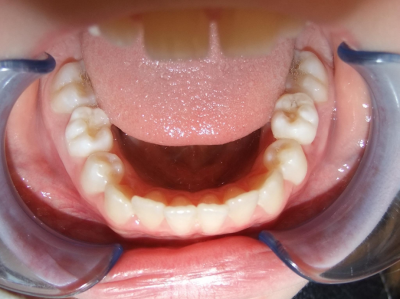

Behandeling Heleen

eindfoto

Leeftijd bij aanvang: 9 jaar

1-6 Bonded Hyrax + volledig vast onderkaak & TransForce